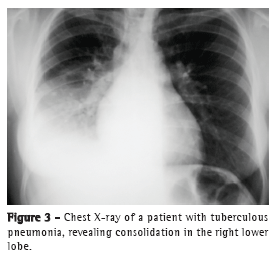

The most common radiological findings are reticular infiltrates and consolidation,(5,6,10,15,17) and cavitation can occur in 27-50% of cases.(6,10,16) Figures 1 to 4 show some of the main radiological patterns in this context.

The time from onset of symptoms to initiation of antituberculosis treatment has been reported to be over 30 days in 28.8-34.0% of cases.(6,17) The time from admission to initiation of appropriate treatment was evaluated in only one study, which reported a mean of 4.3 days. In that retrospective study, the time from admission to initiation of treatment was shorter in patients with miliary tuberculosis than in those with tuberculous pneumonia (2.8 ± 2.5 days vs. 5.0 ± 7.0 days; p = 0.048).(16) There can be a delay in diagnosis and, consequently, in initiation of treatment because it is difficult to differentiate tuberculous pneumonia from severe bacterial pneumonia on X-rays. Considering this difficulty in distinguishing the two pathologies, one study evaluated the differences between ICU patients with severe pneumonia and tuberculosis and those with severe pneumonia without tuberculosis in terms of their clinical and radiological characteristics. Symptom duration longer than two weeks and the presence of micronodules or a cavitary pattern on chest X-ray were significantly associated with active pulmonary tuberculosis.(20) In addition, a miliary pattern on chest X-ray can also be misinterpreted as congestive heart failure.(18)